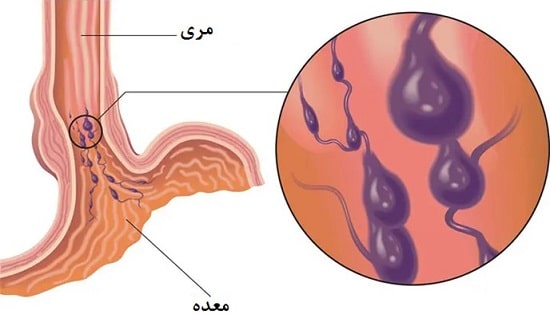

واریس مری، بزرگ شدن غیرطبیعی رگها در لولهای که گلو و معده(مری) را به یکدیگر متصل میکند، رخ میدهد. این مشکل اغلب در افرادی که بیماری شدید کبدی دارند رخ میدهد. واریس مری هنگامی بروز میکند که جریان طبیعی خون به کبد، توسط لخته خون یا بافت زخم در کبد، مسدود میشود. جهت دور زدن این انسداد، خون به رگهای کوچکتری که جهت انتقال این حجم از خون طراحی نشده است، جریان مییابد. خون از رگها نشت میکند یا حتی ممکن است دچار پارگی شود که منجر به خونریزی خطرناک می شود. تعداد زیادی از داروها و روشهای درمانی پزشکی میتواند خونریزی واریس مری را متوقف کرده یا از آن پیشگیری کند. در این مقاله، درباره علائم، علت، درمان و پیشگیری از واریس مری اطلاعاتی را دریافت خواهید کرد. باید بدانید که هر زمان بخواهید رگهای واریسی در ناحیه مری را درمان کنید، باید به یک متخصص باتجربه و ماهر مراجعه کنید که با روشهای درمانی و کنترل عوارض به خوبی آشنایی داشته باشد. این کار خطرات و عوارض جانبی و همچنین زمان بهبودی درمان را کاهش میدهد.

فشار بالای خون در سیاهرگ، (فشار بالای سیاهرگی) خون را به رگهای خونی اطراف پمپاژ میکند که شامل رگهای درون مری میباشد. این رگهای خونی دیواره نازکی دارند و به سطح نزدیک هستند. خون اضافی باعث میشود که آنها بزرگتر شده و متورم شوند. همچنین واریس ممکن است در رگهای خونی کوچک در بخش فوقانی معده ایجاد شود.

اگر فشار ناشی از افزایش خون بالا رود، واریس پاره شده و خونریزی ایجاد میکند. خونریزی یک وضعیت اورژانسی است که نیاز به درمان فوری دارد. خونریزی غیرقابل کنترل میتواند به سرعت منجر به شوک و مرگ شود. همچنین ترومبوز ( لخته خون) در سیاهرگ یا رگ طحال که به سیاهرگ متصل است میتواند باعث ایجاد واریس مری شود.

هر نوع بیماری شدید کبدی ممکن است منجر به واریس مری شود. سیروز کبد یکی از شایعترین بیماریهای کبد است. بیش از 90درصد این بیماران گاهی اوقات در طول زندگی خود دچار واریس مری میشوند و حدود 30% از آنها خونریزی میکنند. در بیمارانی که سیروز کبدی دارند، بخش بزرگی از بافت زخم در سرتاسر کبد ایجاد شده و باعث کند شدن جریان خون میشود. سیروز ممکن است ناشی از بیماری کبد الکلی، بیماری کبد چرب، هپاتیت ویروسی یا دیگر بیماریهای کبد باشد.